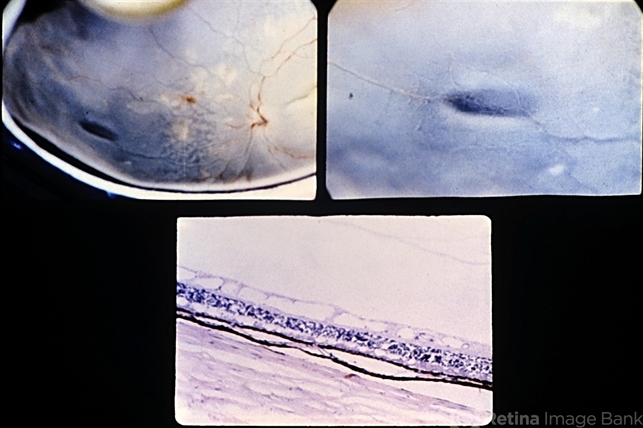

- Radial paravascular rarefaction. This eye with moderate background diabetic retinopathy shows an area of retinal thinning along a major retinal vessel in the midperiphery nasally. This oval area has a reticular appearance (upper views). Histologic section through the area shows the cystic spaces within the nerve fiber layer and an intact overlying vitreous (lower view).